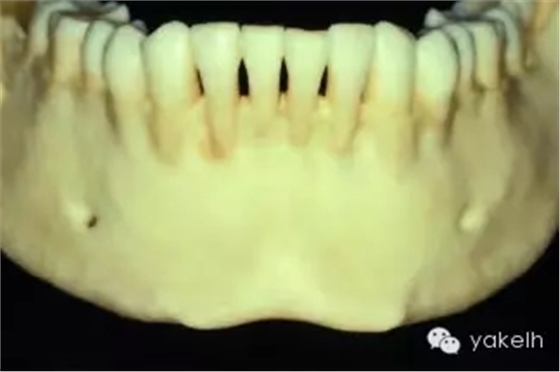

¤¤許多上頜竇以及Onlay植骨的移植物來自于下頜骨頦部。已有報道從下頜骨前牙區(qū)獲取塊狀骨以及顆粒狀骨的技術(shù)。頦部是口內(nèi)能提供最大骨量的區(qū)域(圖13.15)。兩頦孔間的平均距離為5cm,平均厚度為1cm。CT掃描以及全景片能夠評估該區(qū)的可供骨量。頭影測量片可測定下頜骨前牙區(qū)的前后徑。根尖片能更精確地測量牙根長度。

圖13.15 干燥的標(biāo)本提示,從下頜骨頦部可以獲取大量的骨質(zhì)。